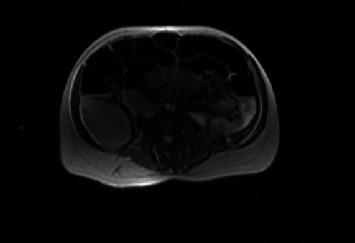

Colorectal cancer (CRC) during pregnancy presents an estimated incidence of 1 : 13,000, and it is associated with diagnostic and therapeutic challenges. Here, we present the case of a 38-year-old woman, 25 weeks and 5 days pregnant, who was transferred to our Obstetrics and Gynecology Department from a local hospital with the diagnosis of intestinal obstruction. Magnetic Resonance Imaging (MRI) showed marked distension with hydroaerial levels of the enterocolic loops upstream of a concentric parietal thickening of the descending colon, stenosing, extended longitudinally for about 4 cm. An exploratory laparotomy was performed with resection of the colon splenic flexure and mechanical end-terminal anastomosis. Histological examination of the operating piece highlighted the presence of moderately differentiated (G2) colon adenocarcinoma (stage pT3N1b). The operation was followed by a single course of oxaliplatin and 5-FU plus leukovorin. The patient had a vaginal delivery at 37 weeks + 2 days of gestational age, following induction of labor and giving birth to a male infant whose weight was 2670 gr with apgar 9/9. We underline the pivotal role of attention to unspecific symptoms, early diagnosis, and active treatment in changing the clinical course of CRC.

妊娠期结直肠癌(CRC)的估计发病率为1:13,000,并且与诊断和治疗挑战相关。在此,我们报告一例38岁女性病例,该女性怀孕25周零5天,因肠梗阻诊断从当地医院转入我院妇产科。磁共振成像(MRI)显示降结肠同心壁增厚上游的肠结肠襻明显扩张,伴有气液平面,狭窄,纵向延伸约4厘米。进行了剖腹探查术,切除结肠脾曲并进行机械端端吻合。手术标本的组织学检查显示存在中度分化(G2)结肠腺癌(pT3N1b期)。手术后给予单疗程奥沙利铂和5-氟尿嘧啶加亚叶酸钙治疗。患者在孕37周+2天经引产阴道分娩,产下一名体重2670克、阿氏评分9/9的男婴。我们强调关注非特异性症状、早期诊断和积极治疗在改变CRC临床病程中的关键作用。